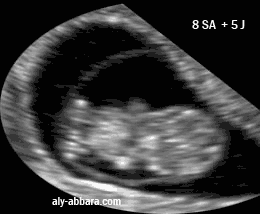

Calendrier de grossesse hebdomadaire et mensuel permettant de calculer l age de grossesse et la date des principaux examens que l on reralise pendant la grossesse comme l echographie et les tests de depistage de la trisomie 21 et enfants le calendrier calcule la date du debut et de la fin du conge de maternite. Découvrez le calendrier de grossesse semaine après semaine il vous permettra de calculer votre semaine de grossesse et vous fournira une multitude d informations sur les différentes étapes de l évolution de votre bébé au cours de la grossesse.